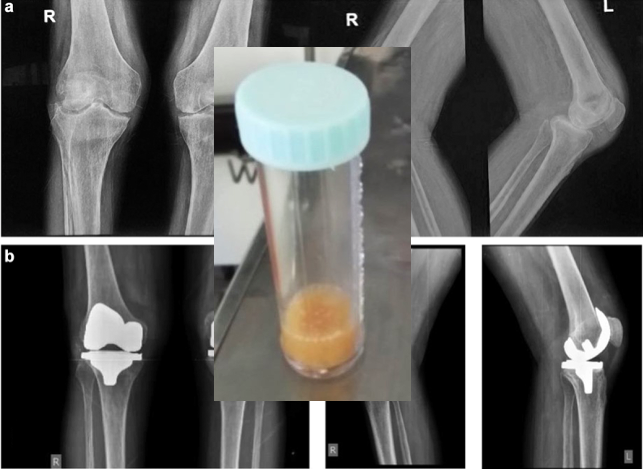

CASE REPORT One-Stage Primary TKA as the Treatment of Acute Septic Arthritis of the Native Osteoarthritic Knee: Report of 3 Cases and Review of Literature Key factors to success: patient selection, intraop technique, and comprehensive antibiotic plan https://t.co/FGUhUgGsJD